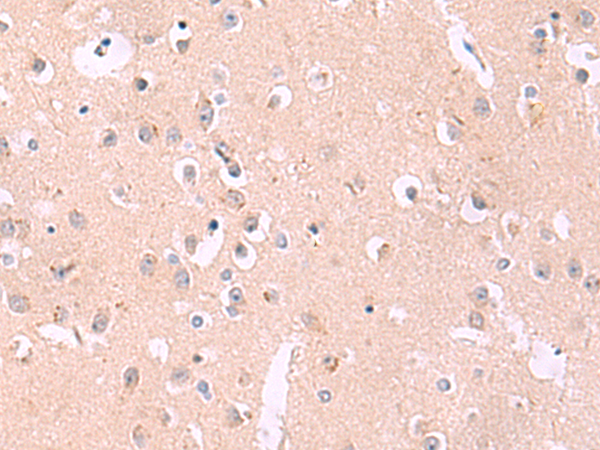

IHC positive control: |

Human brain |